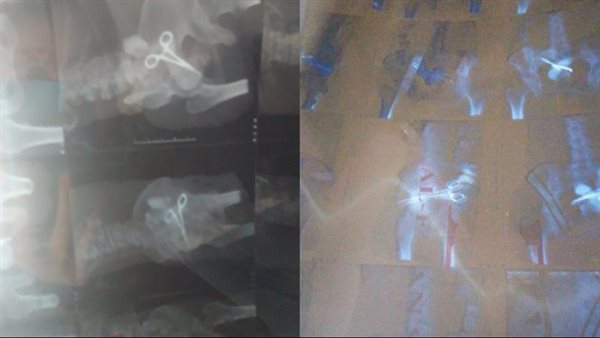

وأردف قائلا: ومن 4 أيام، راحت أختي لأحد الدكاترة، واشتكتله من وجع في منطقة العملية، فطلب منها تعمل أشعة بالصبغة، وبعد ظهور نتيجة الأشعة، لقى الدكتور في الأشعة جيفت (مقص) في بطنها، وسألها الدكتور أنتي عملتي آخر عملية من أمتى فقالتوا في 2017، واستغرب ازاي فضلت عايشة لغاية دلوقتي وفي بطنها مقص معدني.

شقيق نورا عزت: الدكتور اكتشف وجود جيفت كبير في معدتها

وأكمل: طلب الدكتور منها، أنها تعمل عملية في أقرب وقت لإخراج الجيفت، وقالها قبل العملية لازم تثبتي حقك، وتعملي محضر، وبالفعل عملنا محضر في مركز بالزقازيق لإثبات الحالة برقم 866، وهتتعرض على الطب الشرعي يوم السبت، عشان تعمل العملية في القاهرة.